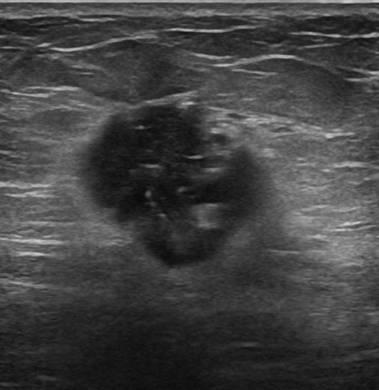

Ung thư vú

» Thông tin: Nữ giới – 51 tuổi.

» Lâm sàng: Khối tuyến vú.